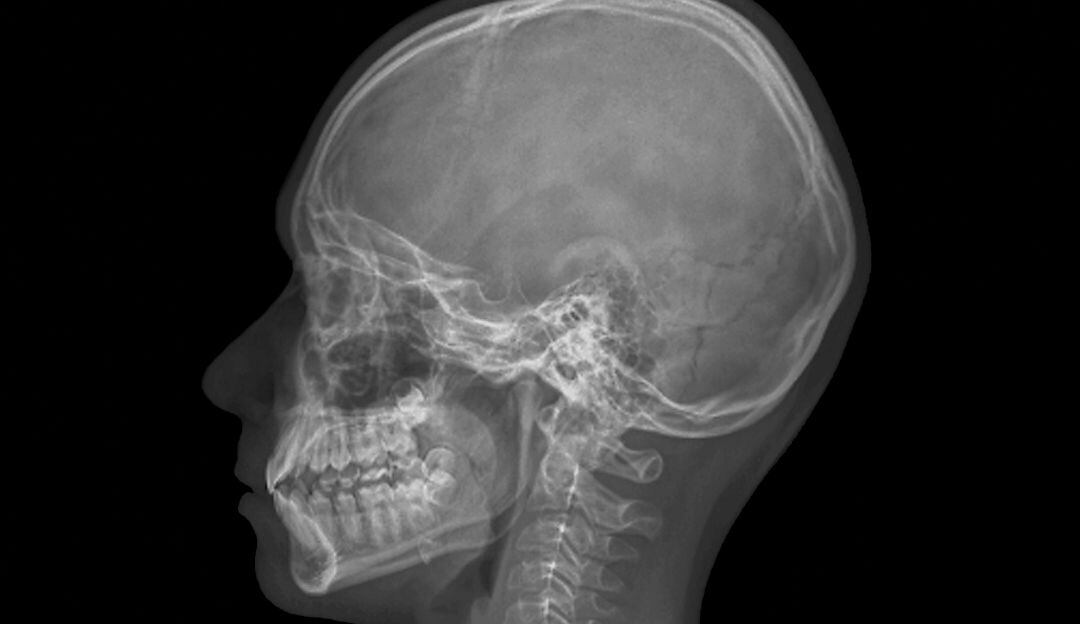

Una sección de los músculos de la mandíbula que hasta ahora había pasado desapercibida, fue descubierta recientemente por científicos de la Universidad de Basilea, Suiza. Dichos científicos han descrito por primera vez en detalle esta parte del cuerpo en la revista Annals of Anatomy.

Este nuevo musculo tiene que ver con una tercera sección más profunda del músculo masetero que eleva el maxilar inferior, esencial para la masticación y la apertura de la boca.

Los científicos, dirigidos pór Szilvia Mezey del Departamento de Biomedicina de la Universidad de Basilea, identificaron una tercera capa "anatómicamente distinta" del músculo masetero luego de analizar más de dos docenas de cabezas humanas, entre ellas la de un sujeto vivo y la de 12 cabezas conservadas en formaldehído.

Los científicos proponen que esta capa reciba el nombre de Musculus masseter pars coronidea –es decir, la sección coronoidea del masetero- porque la capa muscular recién descrita está unida a la apófisis muscular (o "coronoide") del maxilar inferior.